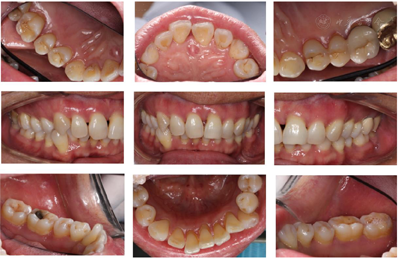

全口临床检查:口腔卫生状况一般,菌斑、软垢少量,下前牙舌侧可见新生牙石,龈下牙石(++)。牙龈色偏红,肿胀,形态圆钝,质软,尤以下前牙舌侧为重,出血指数3~4。全口牙齿探诊深度(PD)5~7 mm,个别位点8~9 mm。全口牙齿均可探及附着丧失,21、24、25、41、43松动I~Ⅱ。46合面金属色充填体,27烤瓷冠复体,近中悬突,可见食物嵌塞,叩痛(-)。咬合关系深覆合,下前牙多生牙,下前牙区拥挤,43位置颊倾,反合,见图1,图2,图3。